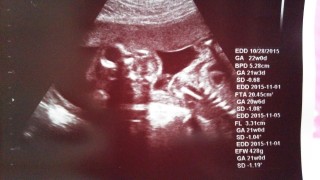

足を丸めてて、性別がハッキリせず、 先生は多分女の子だろうと言っていました。指をおしゃぶりしてるみたいで可愛い!42歳、はじめて授かった子です。 とっても健康と言われて、嬉しいです。